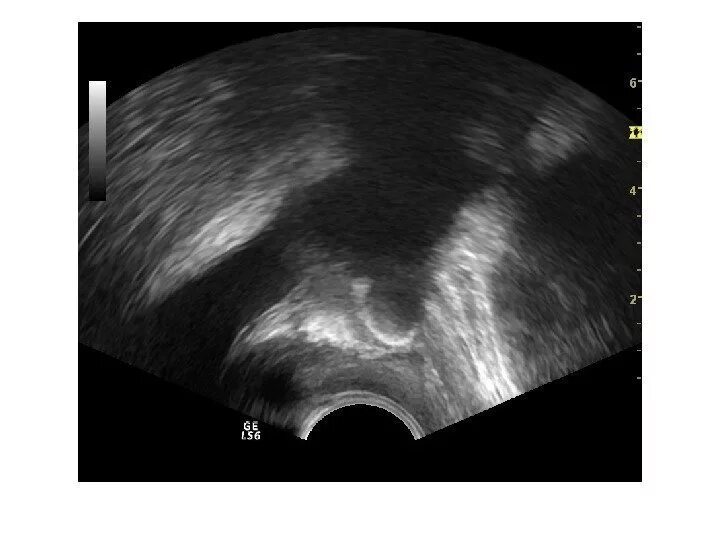

Микрокальцинаты предстательной